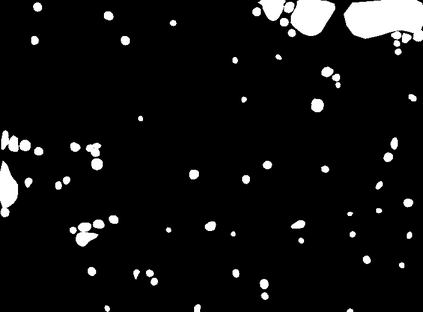

Bright-field microscopy, a cost-effective solution for live-cell culture, is often the only resource available, along with standard CPUs, for many low-budget labs. The inherent challenges of bright-field images -- their noisiness, low contrast, and dynamic morphology -- coupled with a lack of GPU resources and complex software interfaces, hinder the desired research output. This article presents a novel microscopy image analysis framework designed for low-budget labs equipped with a standard CPU desktop. The Python-based program enables cytometric analysis of live, unstained cells in culture through an advanced computer vision and machine learning pipeline. Crucially, the framework operates on label-free data, requiring no manually annotated training data or training phase. It is accessible via a user-friendly, cross-platform GUI that requires no programming skills, while also providing a scripting interface for programmatic control and integration by developers. The end-to-end workflow performs semantic and instance segmentation, feature extraction, analysis, evaluation, and automated report generation. Its modular architecture supports easy maintenance and flexible integration while supporting both single-image and batch processing. Validated on several unstained cell types from the public dataset of livecells, the framework demonstrates superior accuracy and reproducibility compared to contemporary tools like Cellpose and StarDist. Its competitive segmentation speed on a CPU-based platform highlights its significant potential for basic research and clinical applications -- particularly in cell transplantation for personalised medicine and muscle regeneration therapies. The access to the application is available for reproducibility